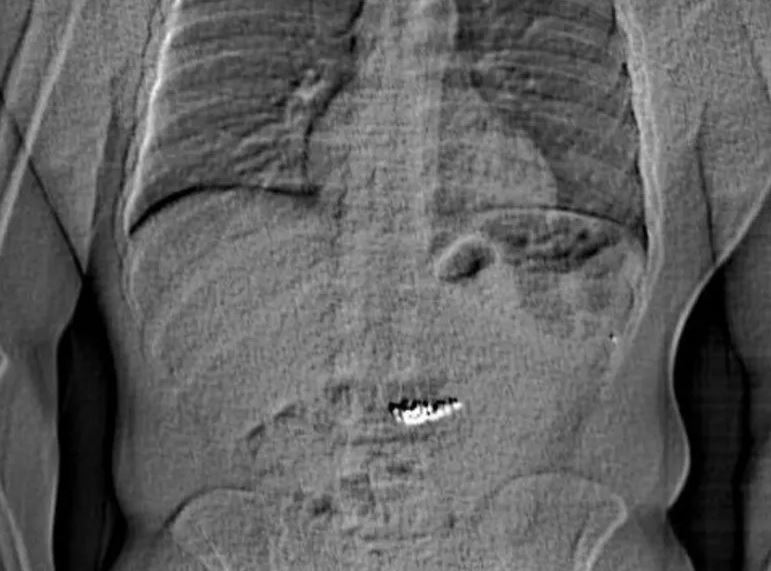

Η ακτινογραφία που, μάλλον, έδειξε τα πειστήρια

Η αστυνομία έδωσε αργότερα στη δημοσιότητα μια ακτινογραφία που φαινόταν να δείχνει την κοιλιά ενός ατόμου με ένα ξένο αντικείμενο στο εσωτερικό της.

Φωτογραφία: Orlando Police